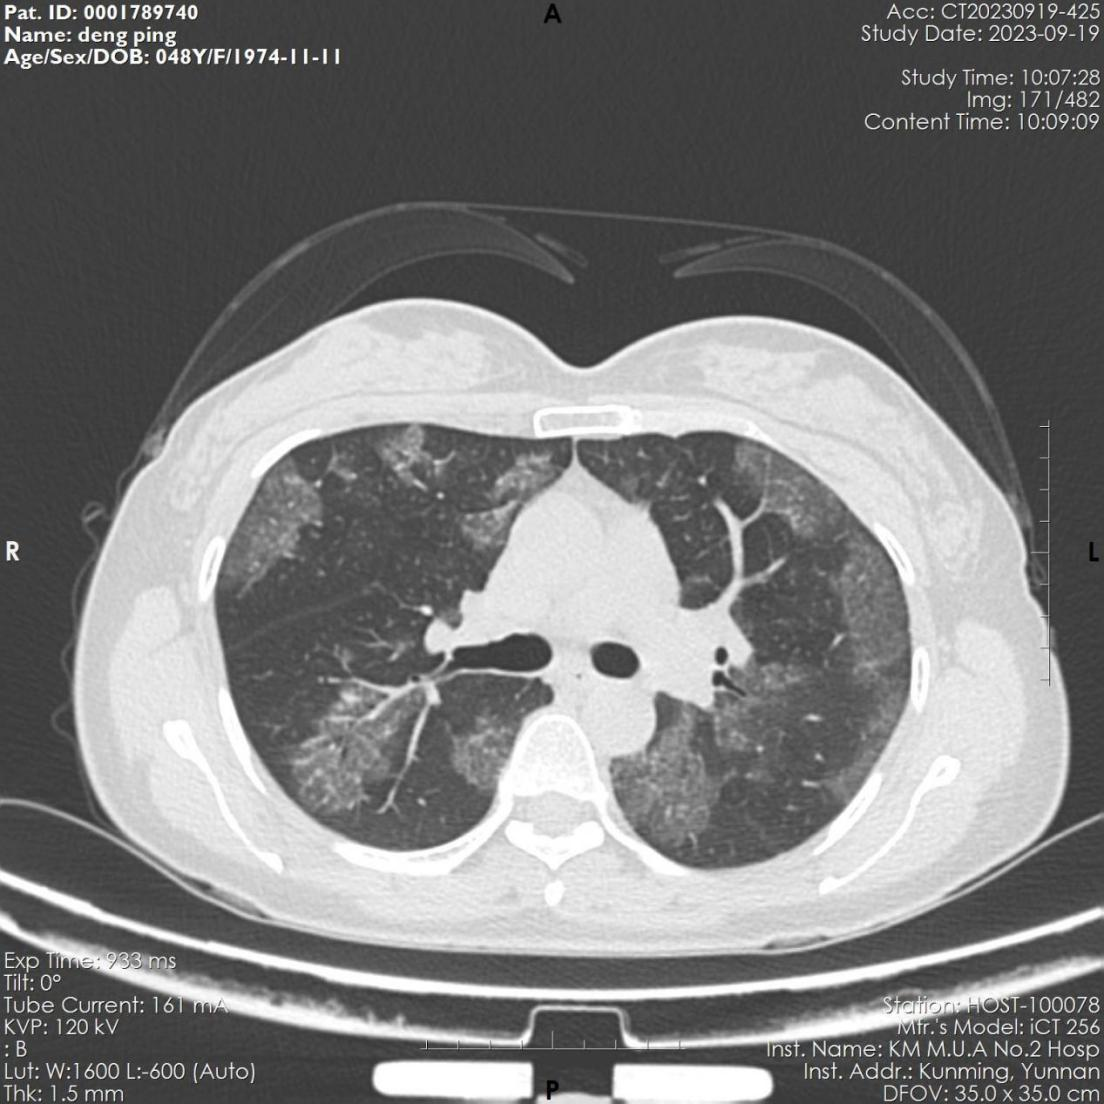

该患者,女,48岁,近3月来反复出现活动后胸闷气促。6月份因感染肺炎住院治疗,经抗病毒治疗后,咳嗽、咽痛等呼吸道症状缓解。9月因胸闷气促再发加重,来到亚洲色吧 附二院全科医学科就诊,复查胸部CT显示肺部病变未见吸收,病变呈弥漫磨玻璃影,病变与正常组织分界较清,呈“地图征”,考虑“间质性肺疾病-肺泡蛋白沉积症可能”收住全科医学科。入院后完善电子支气管镜检查示双侧支气管未见明显异常,但各管腔内的肺泡灌洗液呈乳白色,肺泡灌洗液细胞学病理检查示肺泡巨噬细胞中间粉红色颗粒样物质,D-PAS和PAS染色阳性。结合病史、胸部CT、肺泡灌洗液呈乳白色、PAS染色阳性,该患者确诊罕见病“肺泡蛋白沉积症”。